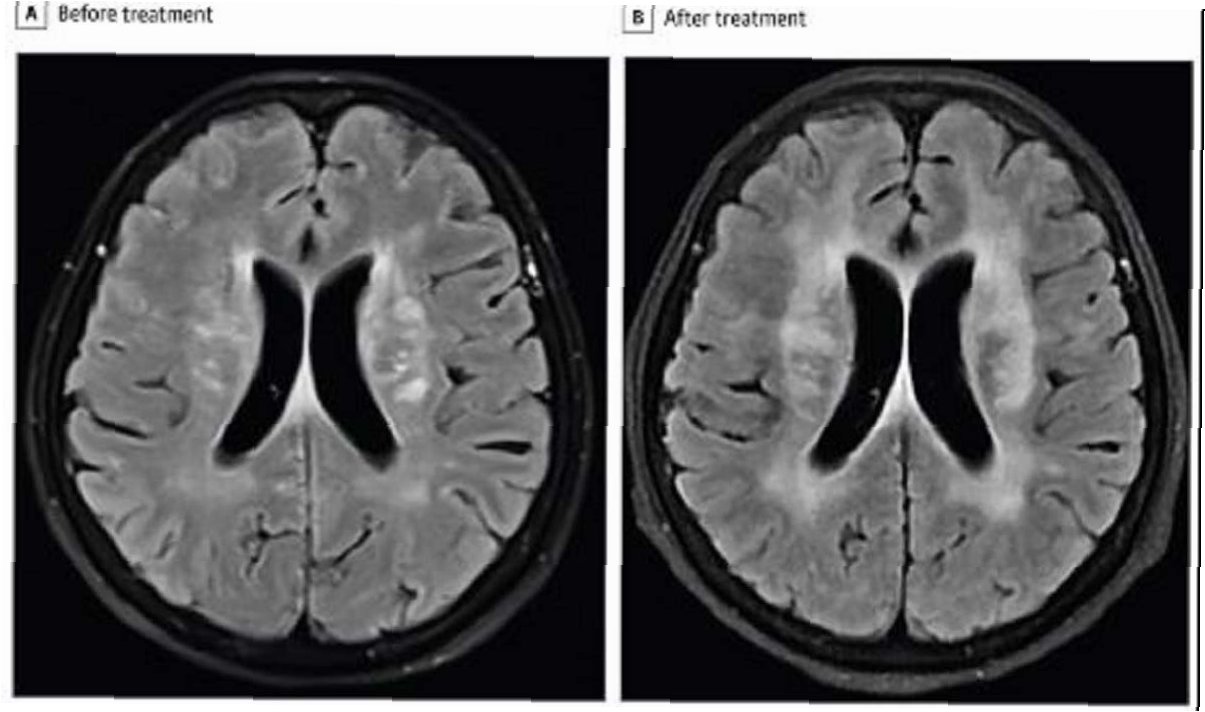

극심한 복통을 호소하며 병원으로 이송된 장씨는 검사 결과 기생충 감염으로 확진되었습니다. 의료진은 소화기관 손상과 함께 스파르가눔을 포함한 기생충이 체내에서 발견되었다고 밝혔습니다. 스파르가눔은 기생충 유충 단계를 의미하며, 이는 장씨가 겪은 고통의 원인이 되었습니다. 이 사건은 개인의 건강을 위해 과학적인 근거 없는 민간요법을 맹신하는 것이 얼마나 위험한지를 보여줍니다.